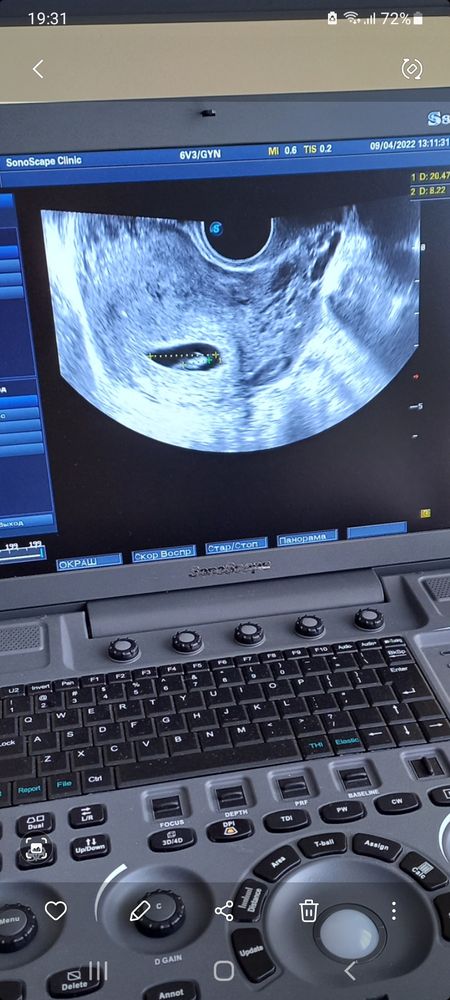

Узи 7 недель

Добрый день. В срок 6 недель врачи узи уже уверены относительно количества человечков внутри😊 поэтому можете быть спокойны - у вас одноплодная беременность (по одной фотографии судить сложно, так как при многоплодной беременности - ребята могут «лежать» в разных плоскостях), но здесь у вас показан один человечек.  удачи и прекрасной Вам беременности!

В 5.5 недель мне всё таки про два плодовых яичка писали. Что-то там есть на фото.